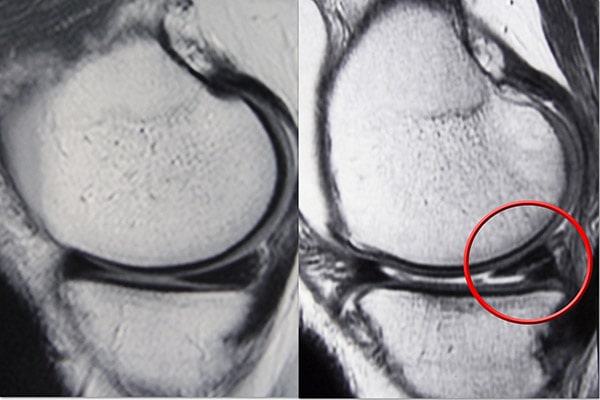

This is a tear where the meniscus is torn and flipped over like a bucket-handle see Figure 2 bottom row left.

6 Meniscus Tear Types That You Need To Know About

Characteristics Of Meniscus Tear In Grade 2 Vinmec